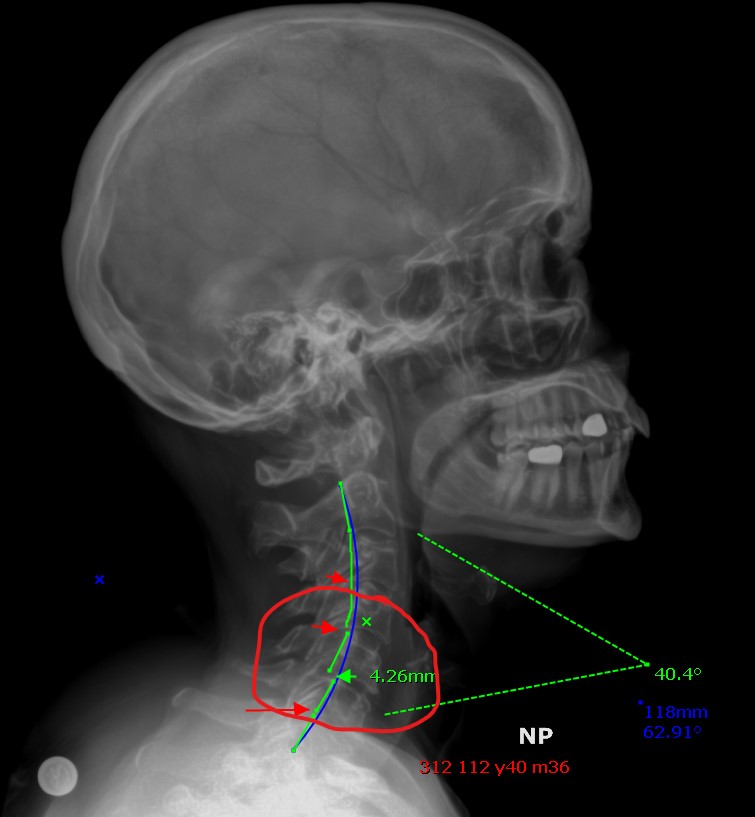

If you look at the area in the red circle above, that's the area that is unstable. Forcefully adjusting there could paralyze the patient. Nothing to worry about since we don't adjust forcefully, right? And since it's imaged, we are aware, so no worries, right? Well, that may be true in our clinical setting, but what about people that get adjusted by doctors who don't utilize x-rays?

This is why we insist on imaging patients first. SAFETY FIRST!